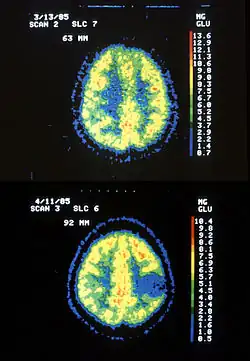

Two PET images—the upper of which shows a normal brain and the lower shows astrocytoma